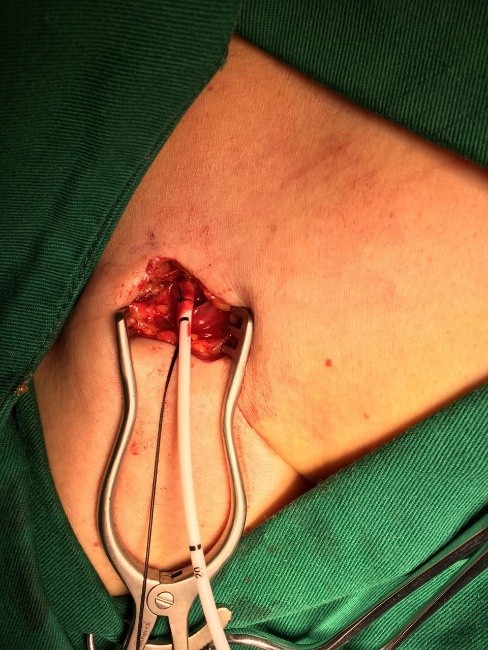

锁骨下小切口找到头静脉,植入输液港导管